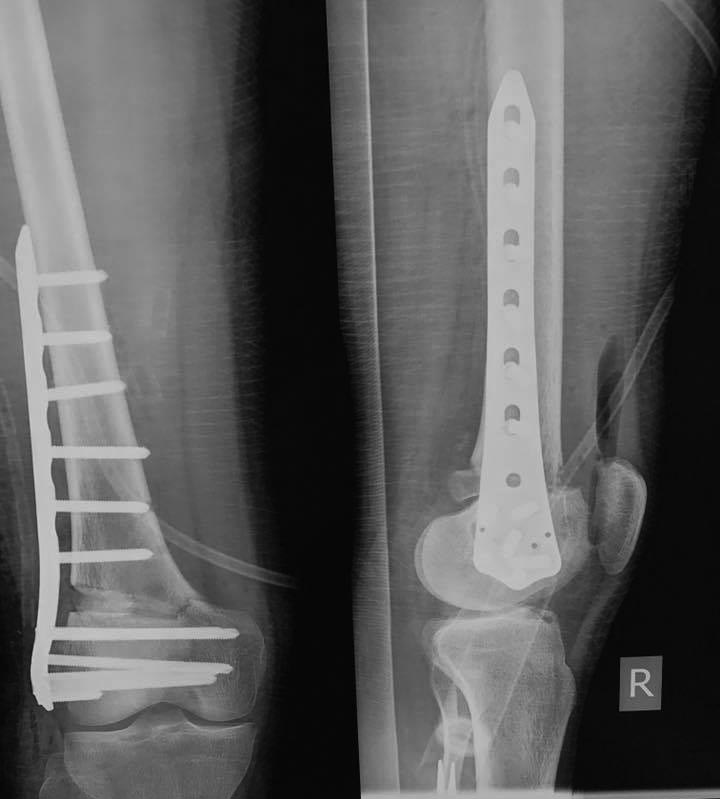

Зачастую после удаления Штифта мы ставим подобную пластину. А протез

можно и после сращения поставить.